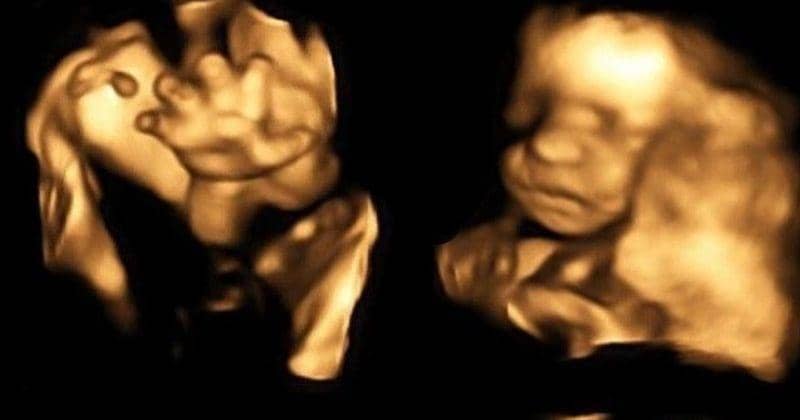

Mungkin Mama pernah merasa penasaran bagaimana cara janin bernapas di dalam kandungan, meskipun mereka tidak bernapas dengan cara yang sama seperti kita. Yuk, pelajari lebih lanjut tentang proses luar biasa ini yang terjadi di dalam rahim.

Di artikel ini, Mama akan menemukan bagaimana janin bernapas, kapan mereka mulai melakukannya, serta apa saja yang terjadi di dalam tubuh mereka selama kehamilan.